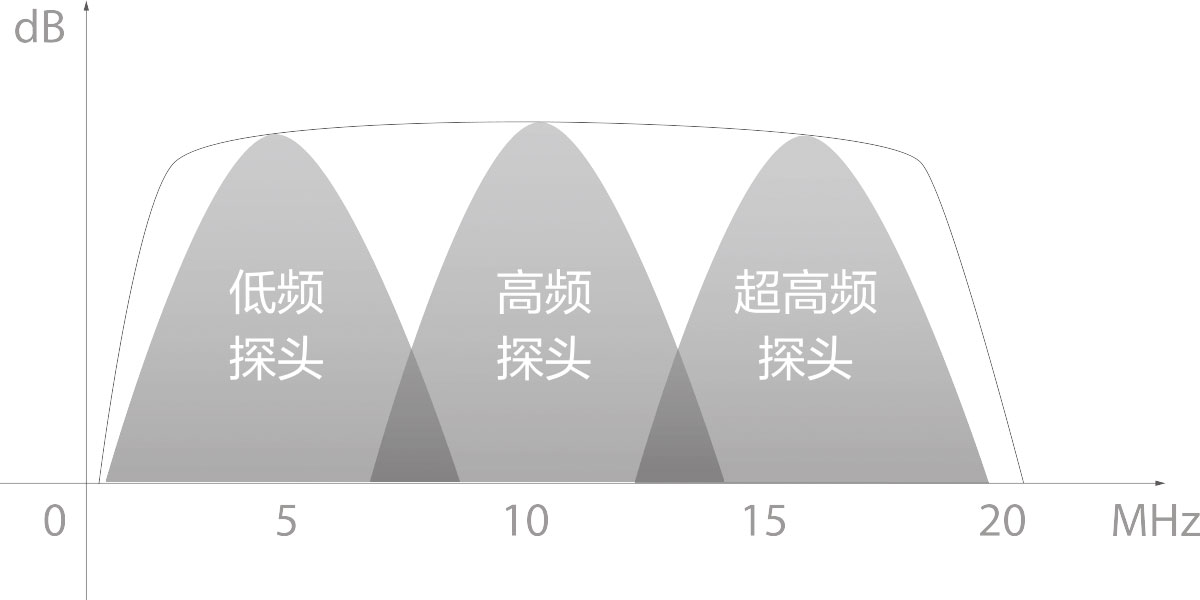

结合竞技宝(JJB)官方网站超宽频带探头技术优势,能够更好地获得高分辨力与高穿透力的平衡,保证图像质量,为临床诊断保驾护航。